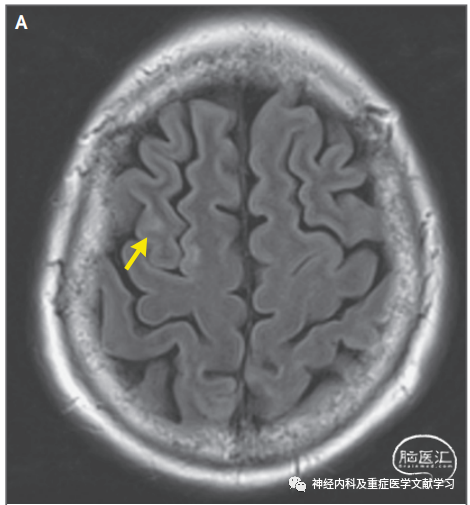

神经影像学是诊断PRES的核心标准。颅脑非增强断层扫描(CT)检查可以发现双侧后循环供血区域明显脑水肿。液体衰减反转恢复和t2加权序列对血管源性水肿更敏感,所以RES影像学诊断磁共振成像(MRI)比CT更准确。MRI信号改变主要发生在双侧枕叶的脑白质区(图1),但也有单侧或灰质受累及其他异常的报道。

58岁男性,急性重度高血压、恶心、呕吐和精神状态改变入院。颅脑磁共振成像(MRI)轴向液体衰减反转恢复(FLAIR)扫描显示主要在双侧枕叶的皮层下和皮层高信号(箭头)。病变区域的弥散加权图像(未示出)正常。颅脑CT可能不像MRI那么明显。